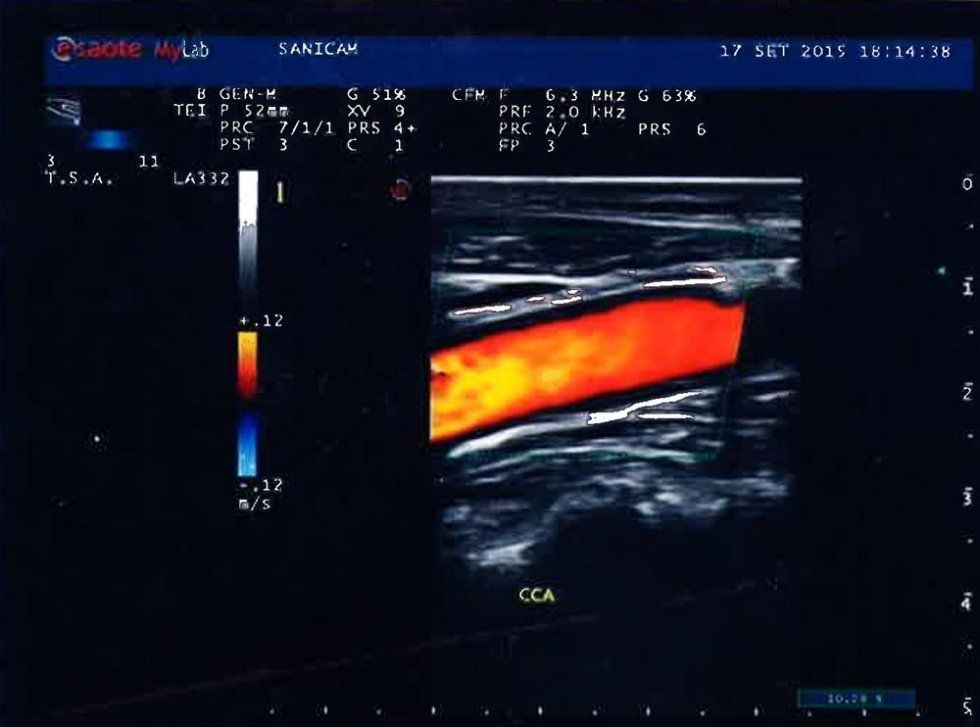

L’eco color doppler è un esame diagnostico sempre più utilizzato in ambito medico per la sua capacità di fornire informazioni precise e dettagliate sul funzionamento del sistema vascolare. Richiesto sia dai medici di base che dagli specialisti, questo esame è non invasivo e consente di valutare tutti i distretti vascolari del corpo, rendendolo ideale per diagnosticare eventuali problemi circolatori come stenosi, occlusioni o insufficienza venosa. L’eco color doppler, infatti, permette di visualizzare in tempo reale il flusso sanguigno all'interno delle arterie e delle vene, grazie all'utilizzo di una tecnologia simile a quella dell'ecografia, ma arricchita dalla rappresentazione a colori del movimento del sangue.

Uno dei principali vantaggi dell'ecocolordoppler è che non richiede l'uso di mezzi di contrasto, a differenza di esami come l’angiografia, che possono essere più invasivi e comportare rischi per i pazienti con allergie o insufficienza renale. In questo esame, il sangue stesso funge da mezzo naturale per la visualizzazione, riducendo così i rischi e rendendo la procedura più sicura.

È una metodica diagnostica strumentale vascolare non invasiva

che utilizza ultrasuoni, onde sonore non percepibili dall'orecchio umano che subiscono deviazioni dalle varie strutture del corpo umano, analizzate da sonde ecografiche che inviano a un computer centrale dove tutto viene elaborato con immagini, colori e suoni.

L'Eco Color Doppler è un esame che permette di valutare aspetto:

ECO; presenza e direzione di flusso:

COLOR; velocità e aspetto del flusso:

DOPPLER; di un area analizzata.